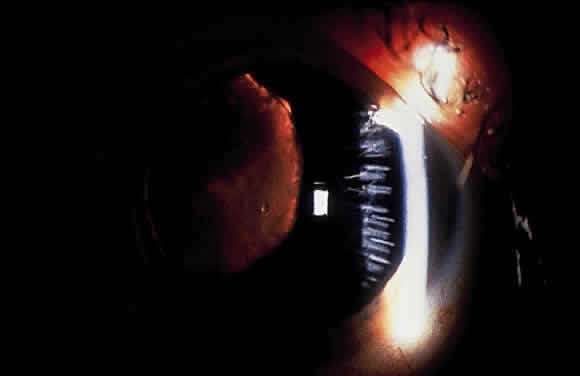

Exfoliative material frequently is observed at the pupillary border (Fig. 4) and should suggest the diagnosis of exfoliation even before the pupil is dilated.27 In addition, defects of the pigmented pupillary ruff are commonly seen. Aasved reports pupillary defects in 6.1% of eyes without XFS and in 74% of eyes with XFS.50 He further notes that in patients with unilateral XFS, pupillary ruff defects were twice as common in the affected eyes when compared with the fellow eyes. Iris transillumination defects in a moth-eaten pattern often are observed. Although these generally are limited to the region of the sphincter (Fig. 5), several patients also have diffuse midperipheral defects.51

Fig. 4. Accumulation of white exfoliative material at pupillary border. (Van Baskirk EM: Clinical Atlas of Glaucoma, p 53. Philadelphia, WB Saunders, 1986)

Fig. 5. Moth-eaten pattern of peripupillary iris transillumination defects seen in exfoliation syndrome.